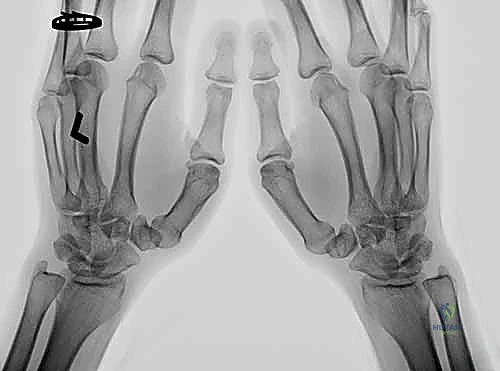

• التصوير الإشعاعي (الأشعة السينية - X-Rays):

لا يكتفي الدكتور هطيف بالأشعة العادية، بل يطلب وضعيات تصوير محددة لتقييم المفصل بدقة متناهية:

• وضعية روبرت (Robert's View): وهي وضعية تصوير أمامية خلفية حقيقية لمفصل الإبهام، تظهر بوضوح المسافة المفصلية وحالة الغضروف.

• أشعة الإجهاد (Stress Views): يتم التقاط الأشعة أثناء قيام المريض بدفع إبهاميه ضد بعضهما البعض، مما يكشف عن مدى الانزلاق أو عدم الاستقرار المخفي في المفصل.